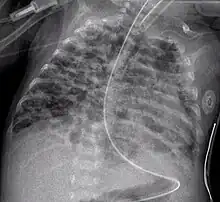

| Radiograph of bronchopulmonary dysplasia | |

- CXR shows with hyperinflation, low diaphragm, atelectasis, cystic changes.